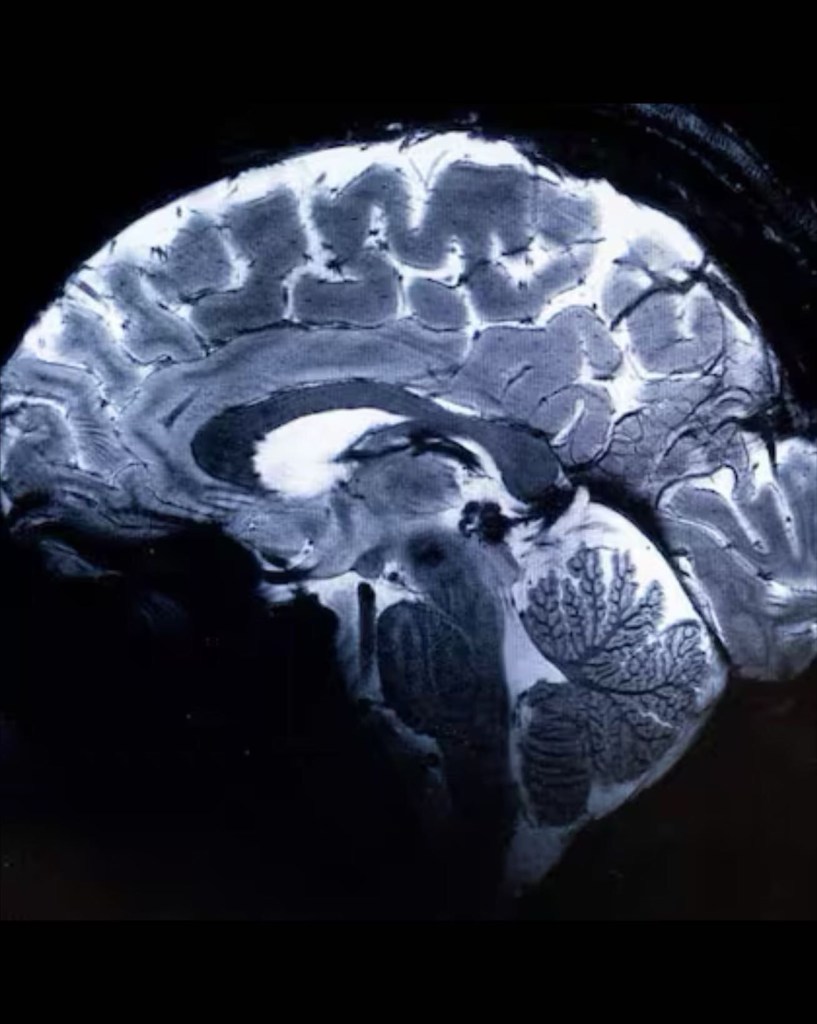

En un estreno mundial, los investigadores de la Comisión de Energía Atómica (CEA) de Francia revelaron este martes una serie de imágenes ‘in vivo’ del cerebro humano, adquiridas con la máquina de resonancia magnética más poderosa del mundo. La Iseult, que cuenta con un inigualable campo magnético de 11,7 teslas y fue construida en un esfuerzo de dos décadas, ha captado el cerebro vivo con una claridad sin precedentes.

Las más notables imágenes anatómicas del cerebro nunca antes obtenidas se tomaron en apenas cuatro minutos. Los expertos señalan que su resolución es impresionante para un lapso temporal de adquisición tan corto. Se logró una resolución en el plano de 0,2 mm y grosor de corte de 1 mm, lo que representa un volumen equivalente a unos pocos miles de neuronas.

En comparación, la misma calidad de imagen requeriría horas con los escáneres de resonancia magnética actualmente disponibles (de 1,5 o 3 teslas). Esto no es realista en la práctica, ya que los pacientes no se sentirían cómodos y cualquier movimiento haría que la imagen se vea «borrosa».